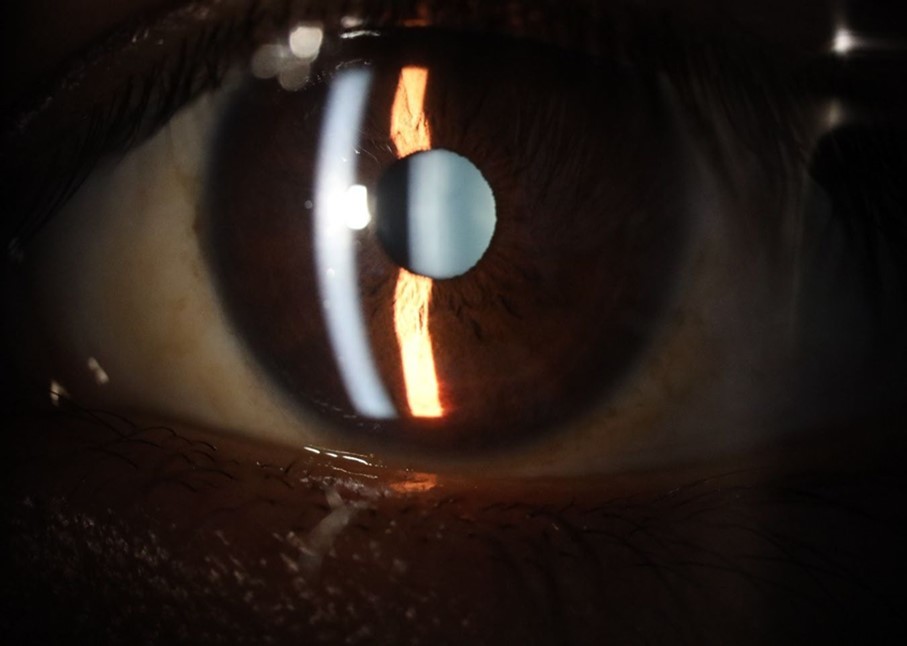

Figure 31.The photograph of the right eye shows an almost normal mirror reflection, as well as a better pupillary dilation.

Figure 32.The macro photograph of the right eye shows us a cornea, anterior camera, and crystalline lens in very good condition.